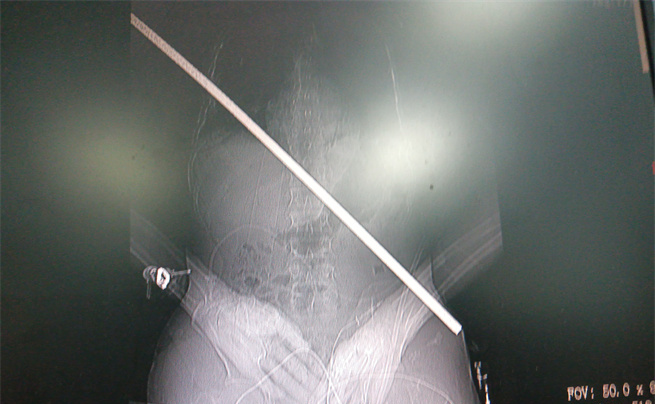

男子身上取出的鋼筋

影像圖。大坪醫院供圖

術中,打開胸腔和腹腔,發現傷者右肺臟已被鋼筋穿透,鋼筋緊貼脊柱,隔肌、橫結腸及小腸系膜等被貫通,幸運地是鋼筋避開了心臟,從下腔靜脈后方、腹主動脈前方穿過。術中還由消化內科文良志副教授行胃鏡檢查排除了食管損傷。放射影像科曹瑞、王承諾技師利用先進的移動CT在手術室行頭顱CT檢查進一步排除了嚴重的顱腦損傷。

由沈岳教授親自緩慢拔出體內長達67厘米的鋼筋。隨后,各組專家各司其職,輪番上陣,為其修補好肺臟、隔肌、腸系膜等破損處。讓大家揪心的是,術中,病人曾雙側瞳孔變大,生命體征一度危急,經醫生努力又將病人從鬼門關拉了回來。